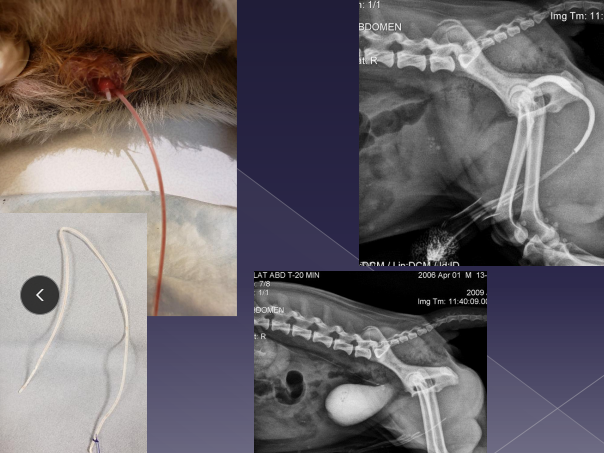

Subcutaneous ureteral bypass (SUB): Obstruction, cats

Replaces ureterotomy, pyelolithotomy

Place catheter from renal pelvis to bladder apex

Ureteral stent: for dogs w/ obstruction

Tx: SUB (C), Ureteral stent (D)